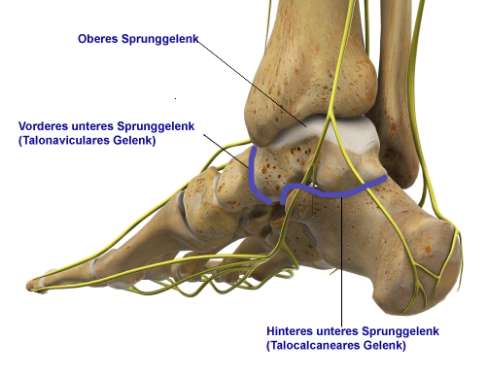

Begriffe:

- Fersenbein (Calcaneus):

Unterstützt das Sprungbein. - Sprungbein (Talus):

Bildet mit den Unterschenkelknochen das Sprunggelenk. - Kahnbein (Os naviculare):

Schließt vorne gelenkig an das Sprungbein an. - Unteres Sprunggelenk:

Wird aus Fersenbein, Sprungbein, Kahnbein und Würfelbein gebildet. - Talocalcaneargelenk (Subtalargelenk): Verbindet Sprungbein und Fersenbein.

- Talonaviculargelenk: verbindet Sprungbein und Kahnbein

Die Double-Arthrodese ist ein chirurgischer Eingriff, bei dem zwei benachbarte Fußgelenke dauerhaft versteift werden, um Schmerzen zu lindern und die Stabilität des Fußes zu verbessern. Sie umfasst die wichtigsten Anteile des unteren Sprunggelenks: das Gelenk zwischen Sprungbein und Kahnbein (Talonaviculargelenk) und das Gelenk zwischen Sprungbein und Fersenbein (Talocalcaneargelenk).